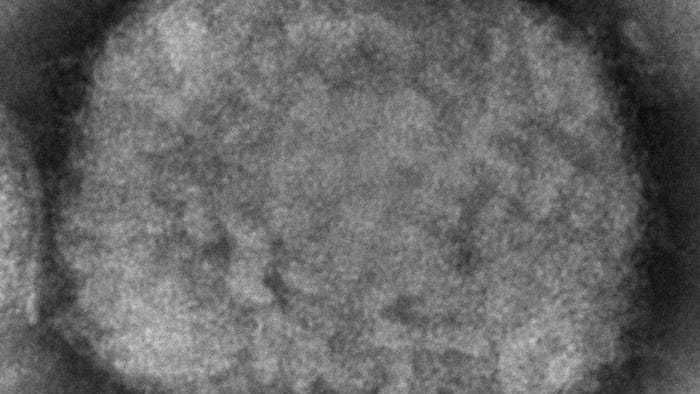

At least 80 cases of monkeypox were recently confirmed around the world, including one in Massachussetts. That's raised some concern not only with health officials, but with the Biden administration as well.

Monkeypox has rarely been identified outside of Africa, so the global spread has prompted questions about the disease. What are the symptoms? Exactly how does it spread?